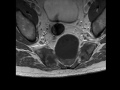

Sacral Chordoma

Patient with pelvic pain.  MR images images demonstrate a T1 hypointense and T2 hyperintense mass arising from the sacrum.  Sacral chordomas often demonstrate a great deal of T2 hyperintensity.  Correlate CT images demonstrate a mass arising from the sacrum with bony destruction.